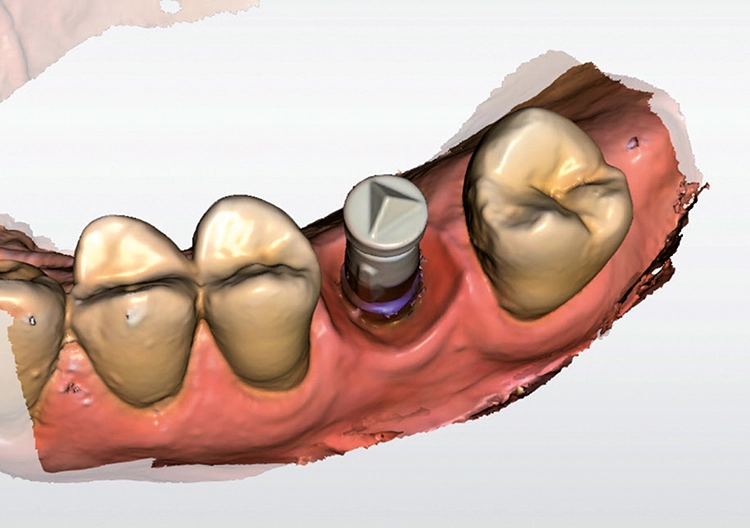

Die Chairside-Fertigung von implantatgetragenen Abutments und Abutmentkronen mit dem Cerec-System brachte Frau Dr. Bernhild-Elke Stamnitz, Langen, dem Auditorium nahe (Abb. 7). Die Referentin differenzierte den Einsatz von individuell gestalteten Abutments gegenüber konfektionierten Suprastrukturen und Hybrid-Abutments sowie den Nutzen der monolithischen Abutmentkrone. Beim zweiteiligen Abutment mit der „Titan-Klebebasis“ greift eine Titanhülse – die von einem verklebten Zirkonoxid-Aufbau ummantelt wird – in den Titan-Enossalpfeiler ein. Stamnitz

Dadurch wird das Risiko der Zugspannung umgangen, die bei direkter Keramikverschraubung entstehen würde. Stamnitz stellte den Nutzen des individualisierten Hybrid-Abutments (Abb. 8) vor, das die mechanische Festigkeit der Titankomponenten, ein anatomisch günstiges Emergenzdesign, einen epigingivalen oder supragingivalen Randverlauf, und eine ästhetische Gestaltung auch bei ungünstiger Implantatposition, umfasst. Stamnitz

Verschraubte Mesostrukturen erleichtern bei Bedarf eine Revision, erfordern aber einen Schraubenschlot, der wenig sichtbar platziert werden sollte. Zementierte Strukturen hingegen können schlanker gestaltet werden, bergen aber bei Zementüberschuss das Risiko einer iatrogenen Entzündung. Zur Vermeidung einer Periimplantitis darf die Abutmentschulter nur leicht subgingival gelegt werden.